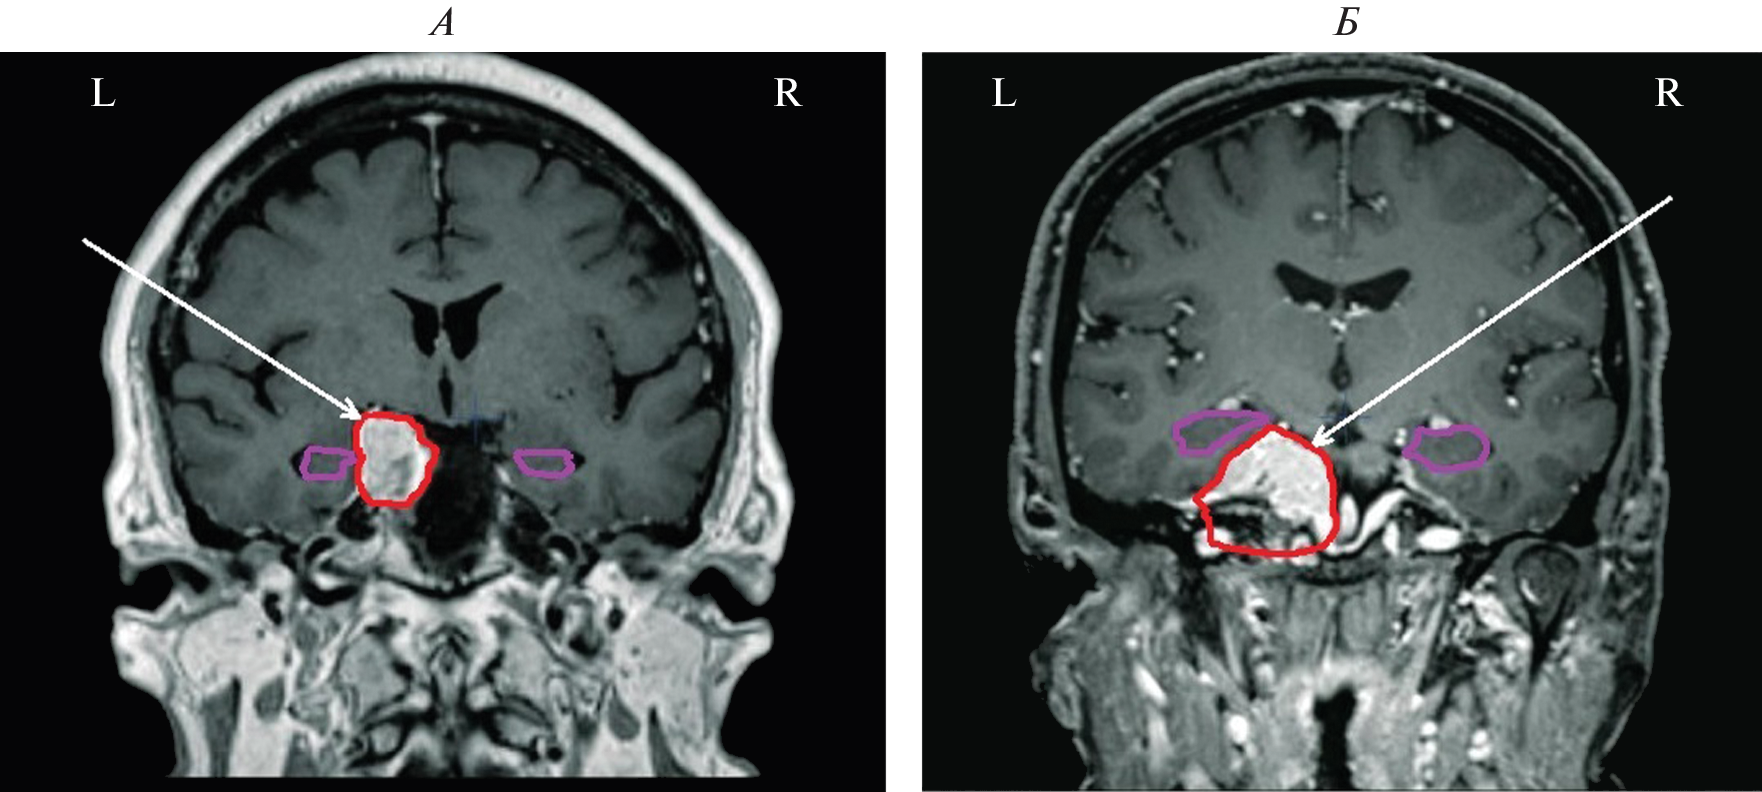

We studied the features of EEG and visual memory processes in 27 patients with a mediobasal regions extracerebral tumor of right and left hemispheres. According to neuroimaging (MRI) and morphometry, the degree of hippocampus involvement in pathological process was assessed. The predominant concentration of irritative-epileptiform signs in the affected hemisphere, as well as the presence of atypical alpha-rhythm episodes in the tumor projection zone, were classified as EEG markers of tumor compressive effect on the hippocampus. Signs of non-identical involvement of the right and left hippocampi in the pathological process were found in the form of a predominance of irritative signs in the left hemisphere throughout the group as a whole. Equivalent dipole sources (EDS) of atypical alpha rhythm are more confined to hippocampal structures than irritative EEG patterns. Neuropsychological testing of visual memory did not reveal significant disturbances in memory processes at this stage of the disease.

- Kazda T., Jancalek R., Pospisil P. et al. Why and how to spare the hippocampus during brain radiotherapy: the developing role of hippocampal avoidance in cranial radiotherapy // Radiat. Oncol. 2014. V. 9. № 1. P. 139.

- Kim K., Wee C., Seok J. et al. Hippocampus-sparing radiotherapy using volumetric modulated arc therapy (VMAT) to the primary brain tumor: the result of dosimetric study and neurocognitive function assessment // Radiat. Oncol. 2018. V. 13. № 1. P. 29.

- Кроткова О.А., Кулева А.Ю., Галкин М.В. и др. Факторы модуляции памяти при лучевом воздействии на гиппокамп // Соврем. Технол. Мед. 2021. Т. 13. № 4. С. 6. Krotkova O.A., Kuleva A.Yu., Galkin M.V. et al. [Memory modulation factors in hippocampus exposed to radiation] // Sovrem. Tehnol. Med. 2021. V. 13. № 4. P. 6.